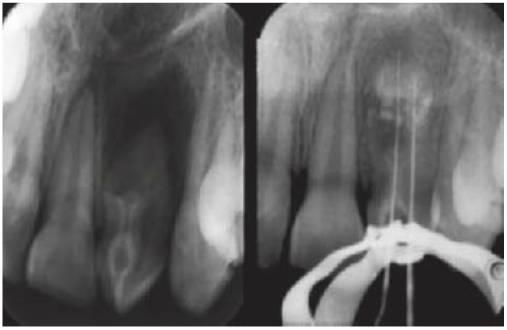

Dens invaginatus

Los incisivos laterales maxilares pueden presentar una invaginación (consecuencia del desarrollo) de la fosa cingular que presenta con frecuencia tan sólo una fina barrera de tejido duro que separa la cavidad oral y la pulpa. Suele producirse una necrosis pulpar poco después de la erupción del diente afectado y puede ocasionar un absceso o una celulitis en la fosa canina. Esta anomalía puede aparecer en otros dientes, como los incisivos centrales y caninos superiores (figs. 9 19,9.20).

Tratamiento

- Si ha erupcionado de forma reciente, se puede prevenir mediante el sellado de las fisuras de la superficie palatina.

- Si hay caries, colocar una resina de composite tras un grabado ácido.

- Si el diente es asintomático y la morfología del conducto radicular resulta favorable, se puede llevar a cabo el tratamiento endodóncico.

- Si la anatomía interna es compleja y el conducto radicular no resulta accesible, en caso de infección se procederá a la extracción del diente. Se debe analizar de forma exhaustiva la presencia de esta anomalía durante la planificación del tratamiento ortodóncico.